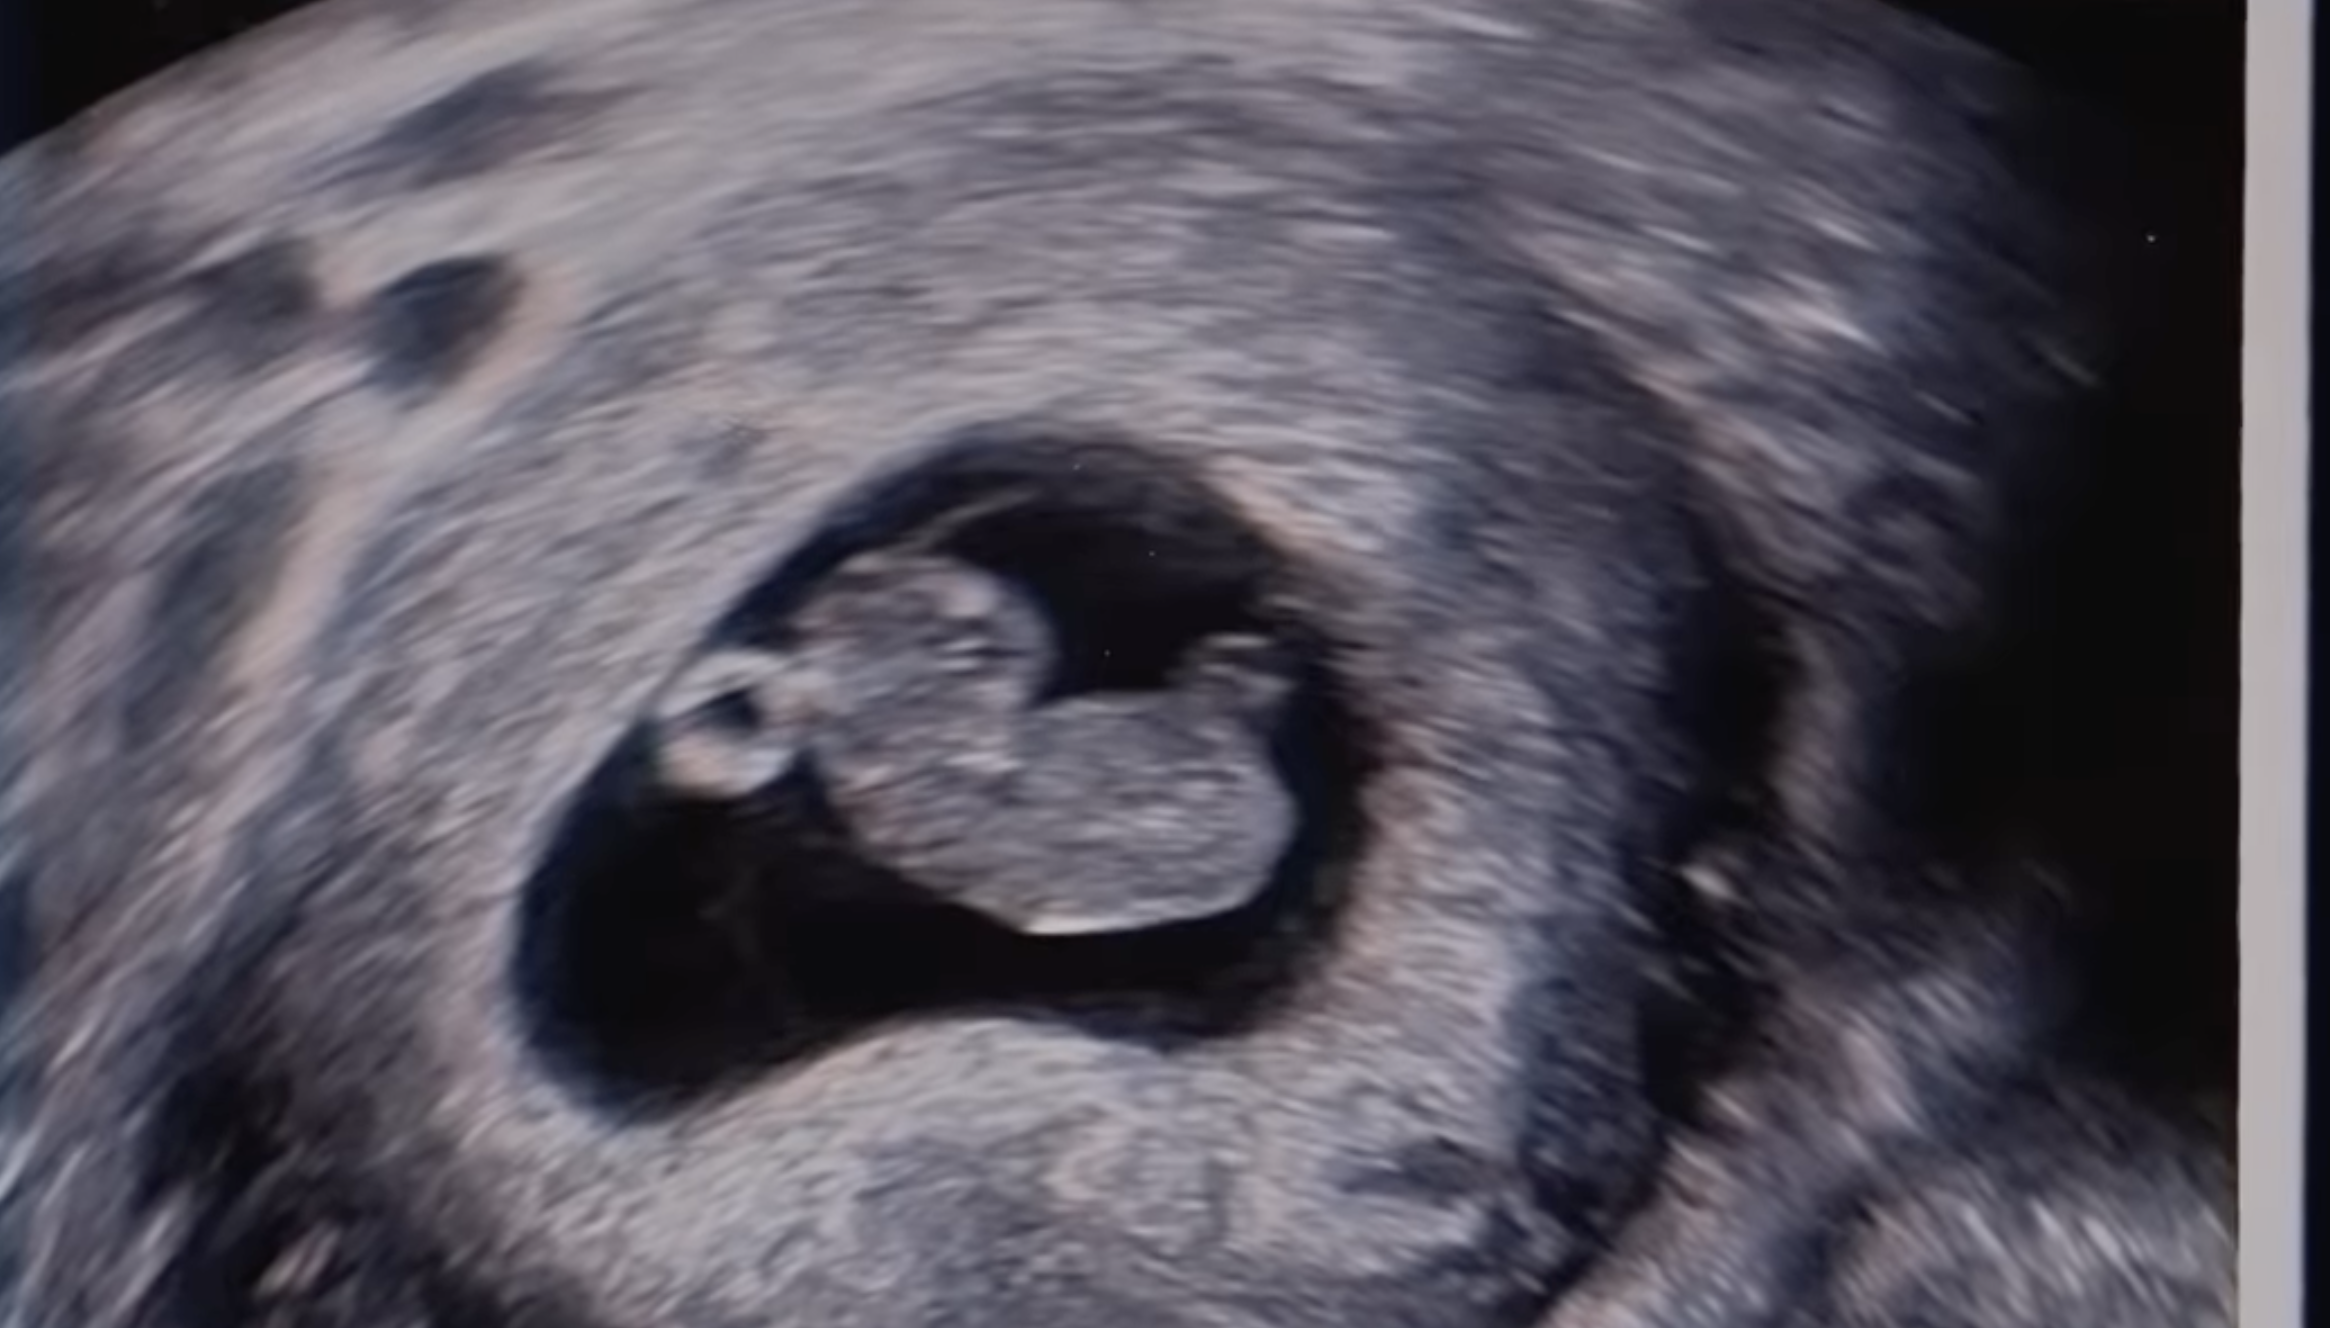

Fiica lui Eminem este însărcinată! Hailie și tatăl ei au făcut anunțul în cel mai indedit mod posibil